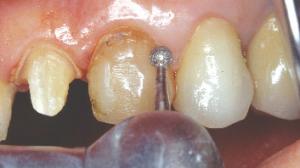

Une fraise à congé termine la préparation vestibulaire.

La préparation de la face vestibulaire est terminée. La limite est pour le moment supra gingivale.

Dans le cas d'une canine, il faut englober la concavité. La fraise boule réunit en palatin les congés proximaux en traçant un sillon palatin apicalement au contact occlusal. Le bord libre sera diminué de 1 mm.

Le contact occlusal se fera sur la céramique. Un espace de 1 mm a été ménagé entre la préparation et la dent antagoniste avec la fraise boule.